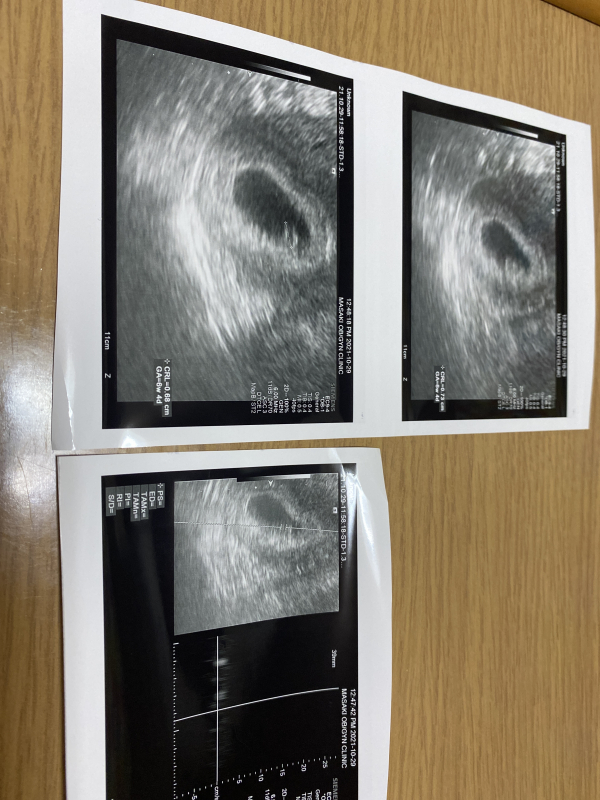

第二子を妊娠したいるのですが、心拍を確認するには端っこ?にいて聞き取りづらいと言われ、心拍も薄ーく聞こえる感じでした。一応心臓は動いてから大丈夫とは言われたのですが 心配です。

※ 閲覧に注意が必要な画像が含まれている場合がございます。